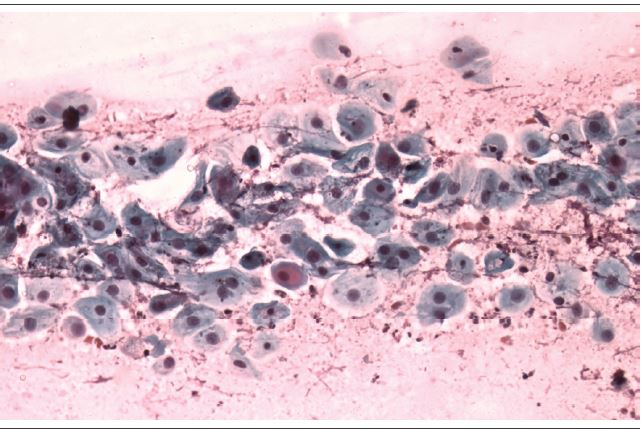

From the total of 20 abnormal cases (4%) of samples evaluated (Figures 1 and 2), four (20%) took hormones: two cases were classified as atypical squamous cells - cannot exclude high-grade squamous intraepithelial lesion [(ASC-H) - 10%], and two as atypical squamous cells of undetermined significance [(ASC-US) - 10%]. There was no statistically significant difference between the lesion degrees and the age of the patients (Table 2).

When associated with vaginitis, the identification of alterations in the atrophic epithelium presents diagnostic difficulties, since parabasal cells can degenerate, resulting in a pattern of autolysis, resembling tumor cells. The granular material at the background of the slide resulting from this degeneration may also be mistaken for tumor diathesis(8,12).